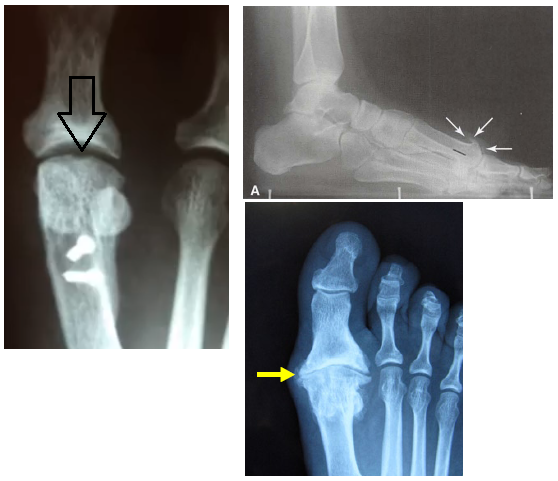

• Quais as principais alterações na radiografia?

A

• Depressão no domo da cabeça do 1° metatarso (artrose inicial)

• Artrose na art. mtfl

• Osteófito dorsal na cabeça do 1° mtt

How well did you know this?

• Na avaliação radiográfica, qual o 1° sinal radiográfico a aparecer?